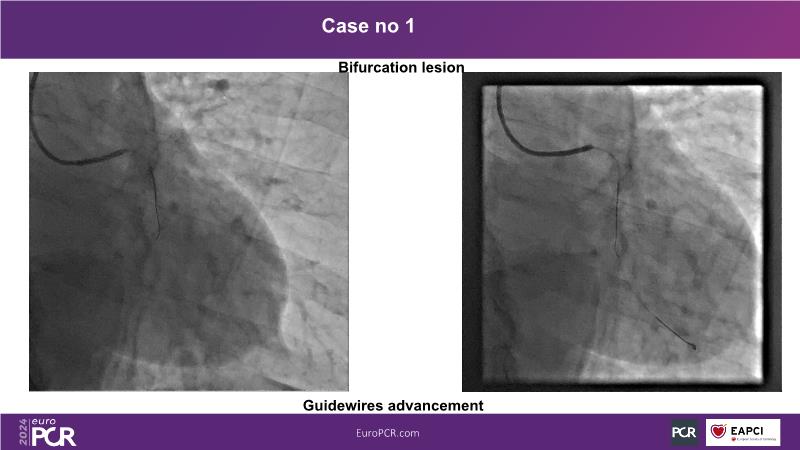

In this session, discover the effectiveness and safety of robotic PCI for both simple and complex lesions requiring additional devices like IVL, IVUS, laser, and FFR. Learn about the numerous benefits of robotics for patients and cathlab teams, including enhanced precision in wire navigation and stent positioning, full radioprotection, and reduced orthopedic injuries. Explore the growing interest in robotics within the interventional cardiology community, anticipate future technical advancements, and understand how AI will accelerate the integration of robotics and vice versa.

- To learn about a robotic PCI step-by-step from real-life experience